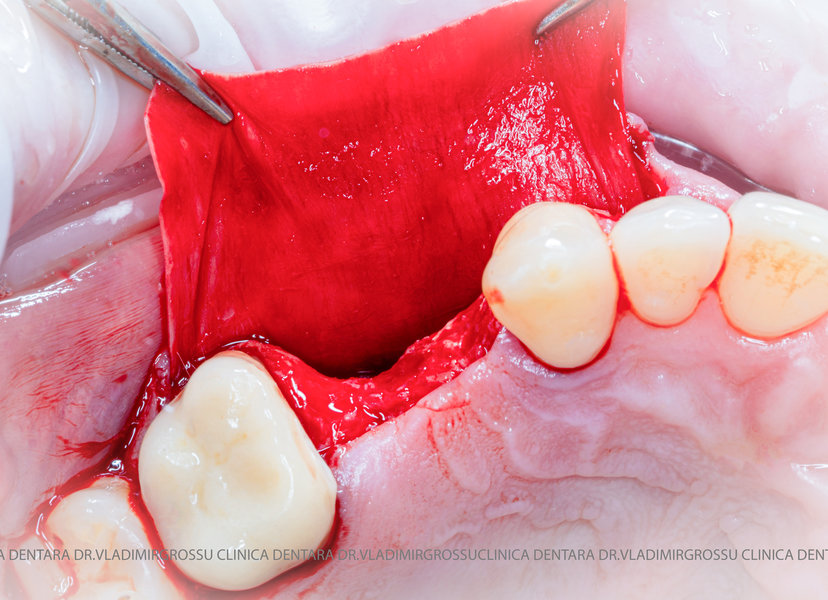

Un element esențial în procedura de aditie osoasă este utilizarea membranelor biologice, care izolează materialul osos de țesuturile moi (gingie) pe durata procesului de vindecare. Cele mai recomandate sunt membranele resorbabile din colagen sau pericard.